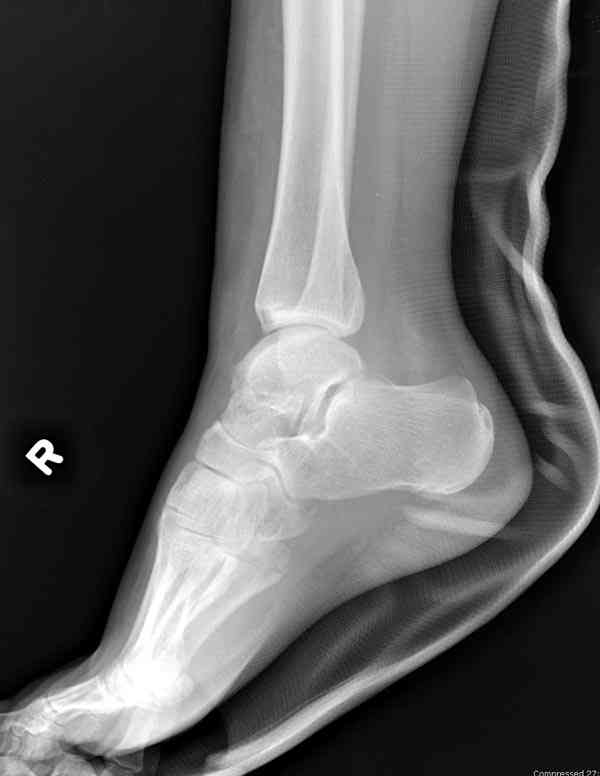

Interesting case

The ankle joint looks ruined. I wonder howcome is it as ruined after 2 days. I would open the joint( Some people would artroscope it) and judge the osteosynthes vs ankle fusion according to the ankle joint condition. The subtalar does not look injured, but if you feel there is a clinical

problem- CT it. Above all- when I see such an X-Ray I call the resident who ordered it and tell him that I would expect him first thing to reduce it on arrival since the soft tissue suffer and I hope that currently the p-nt is reduced to some extent at least.

а основании двух видов ренгенограмм невозможно радикально решить о необходимости открытой репозиции или первичного артродеза.

Для оценки состояния нужны дополнительные исследования, например Canale или Broden ренгенограммы и Компьютерная томография.

При переломах тарана всегда имеется риск AVN, а классификация Hawkins поможет разобраться с предполагаемыми осложнениями.

Если в первом типе, когда перелом шейки без смещения, тогда AVN менее 10%, при втором типе когда имеется смещение и вывих тарана в субталарном сочленении меньше 40%, а при типе III когда смещение в голеностопном и субталарном суставах - около 90% и в типе IV, когда происходит полный вывих, риск AVN достигает 100%.

Для оценки состояния нужны дополнительные исследования, например

> Canale или Broden ренгенограммы

повторили рентгенограммы и доделали проекции, к единому мнению все еще не пришли

На ренгенограмме не уловил многоскольчатость тарана, чтобы доказать, конечно, можно было исследовать на КТ, потом КТ дает ориентацию фрагментов.